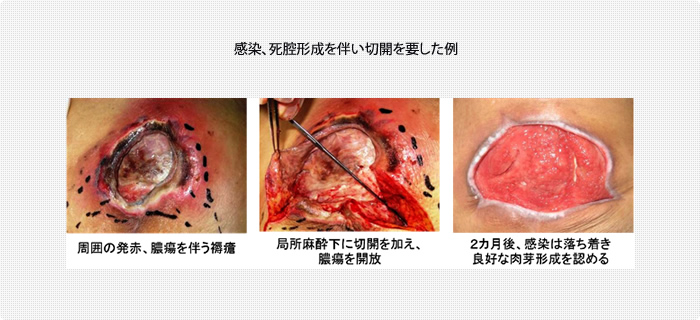

実践します!褥瘡ケア「いつもの方法を見直してみよう」エール在宅診療所。

実践します!褥瘡ケア「いつもの方法を見直してみよう」エール在宅診療所。

褥瘡のポケット形成について - 東御市民病院・東御市立みまき温泉診療所・東御市立助産所とうみ。

実践します!褥瘡ケア「いつもの方法を見直してみよう」エール在宅診療所。